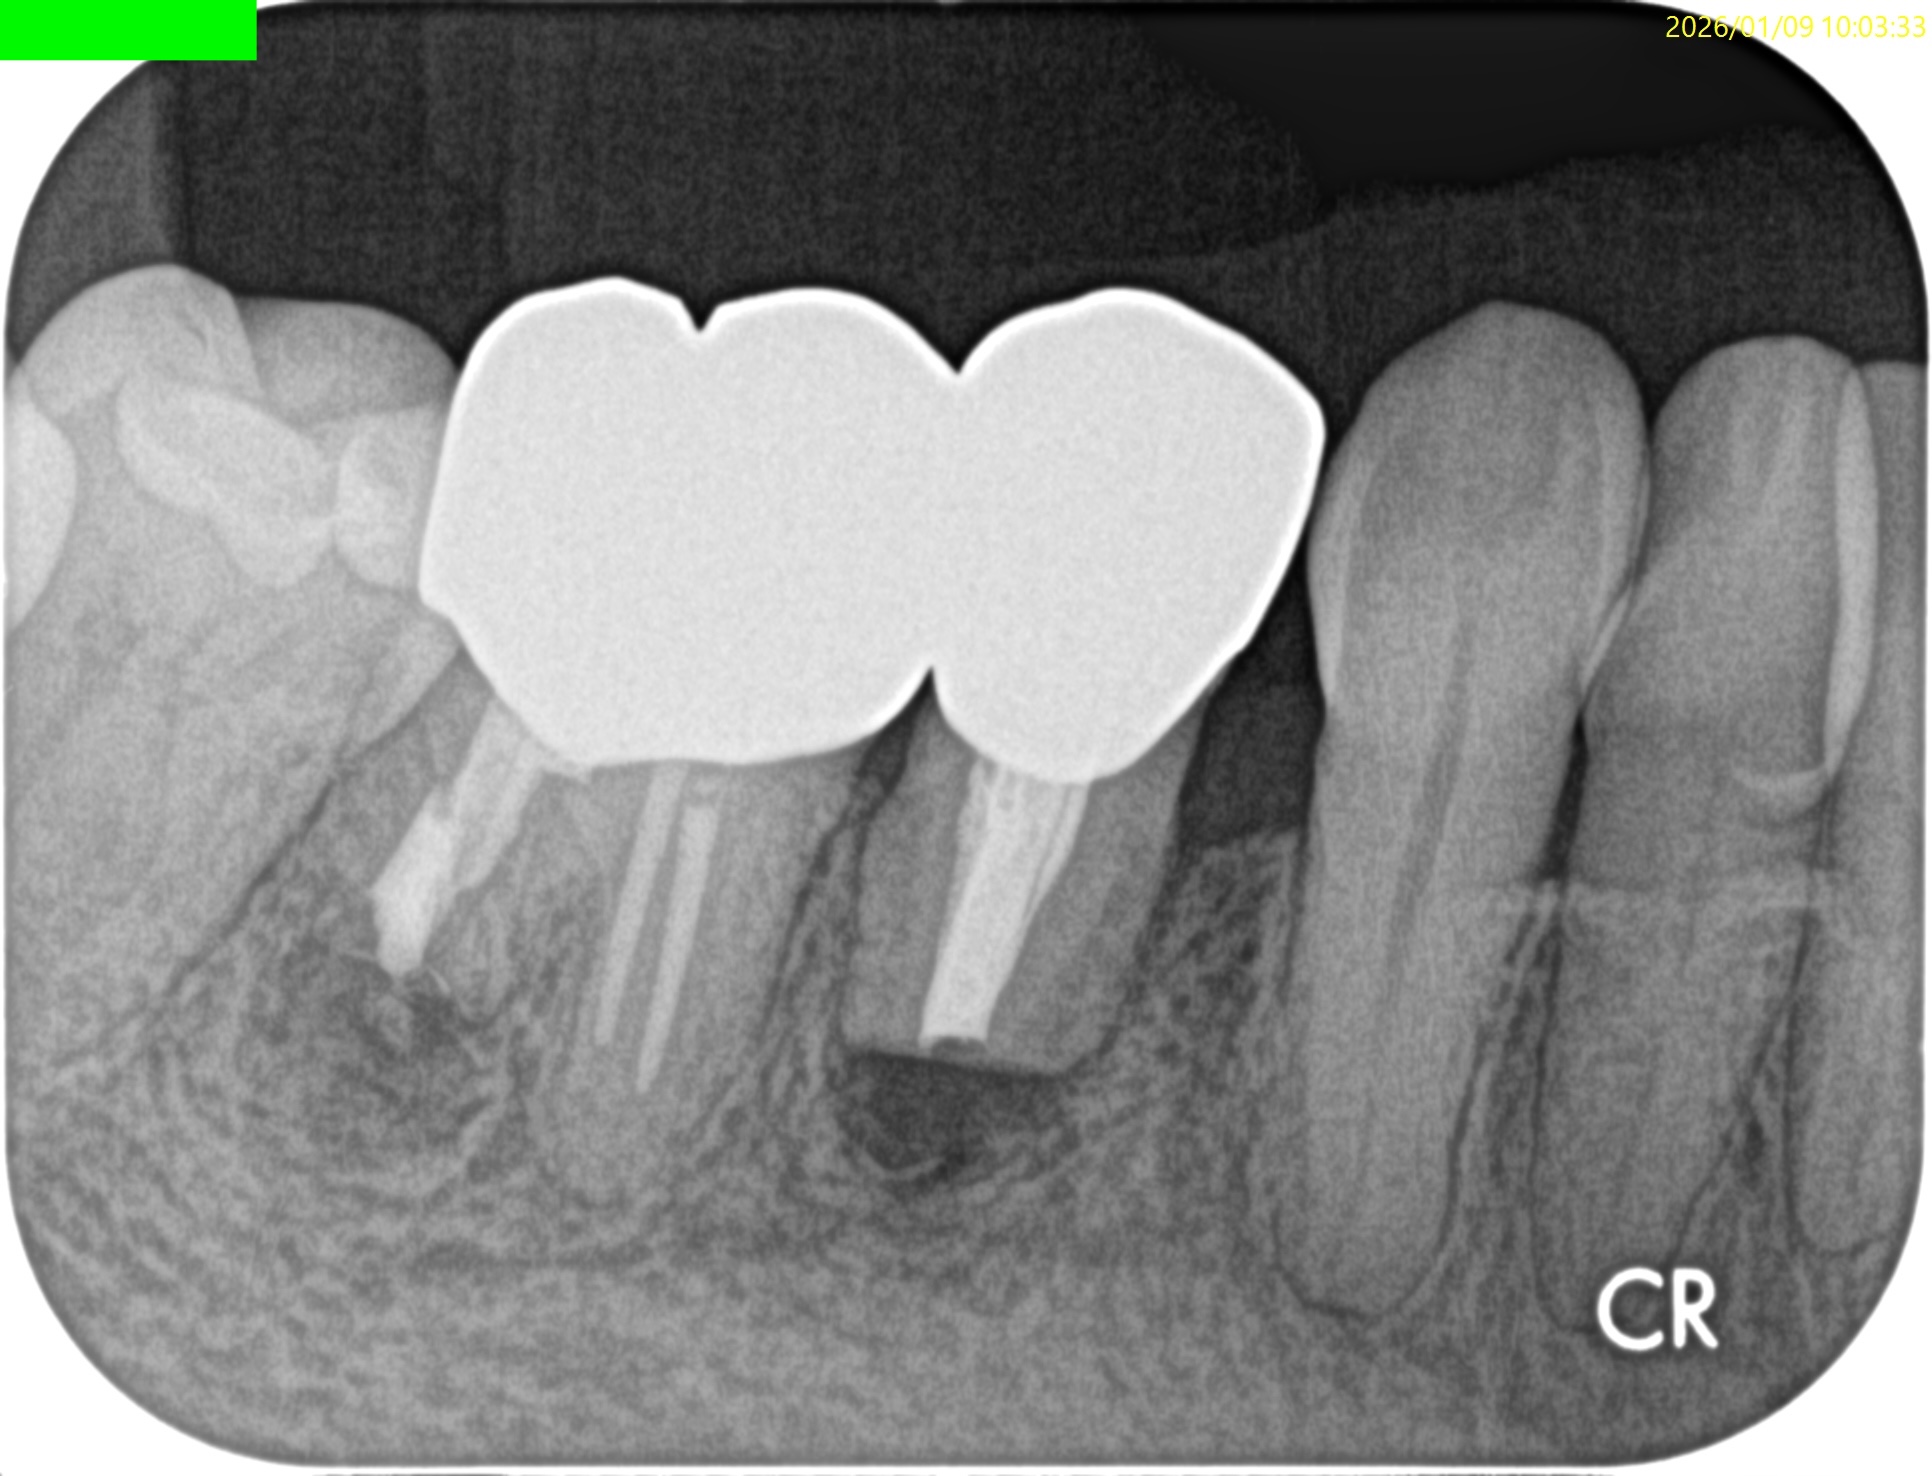

#29 Intentional Replantation 2M recall(2026.1.9)

PA, CBCTを撮影した。

歯槽骨は順調に回復している。